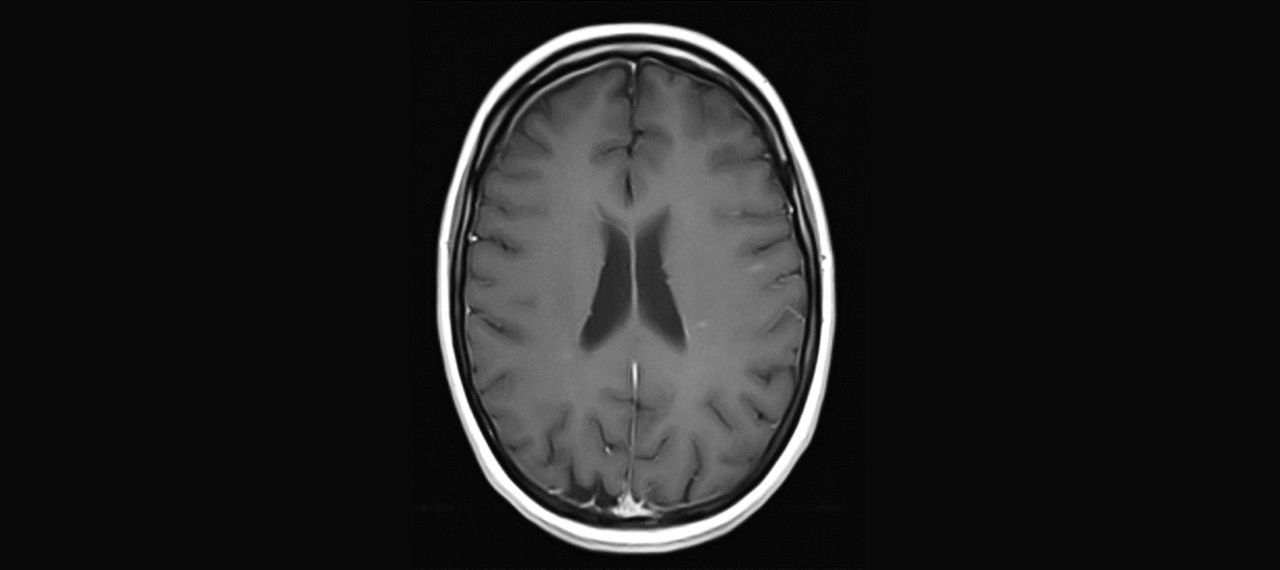

Abb.1: Periventrikuläre Läsionen in T2

Abb.2: T1+KM

Abb.3: PD

Herd im cervikalen Myelon: kurzstreckig, ungefähr 1 cm groß

Abb.4: T1 + KM